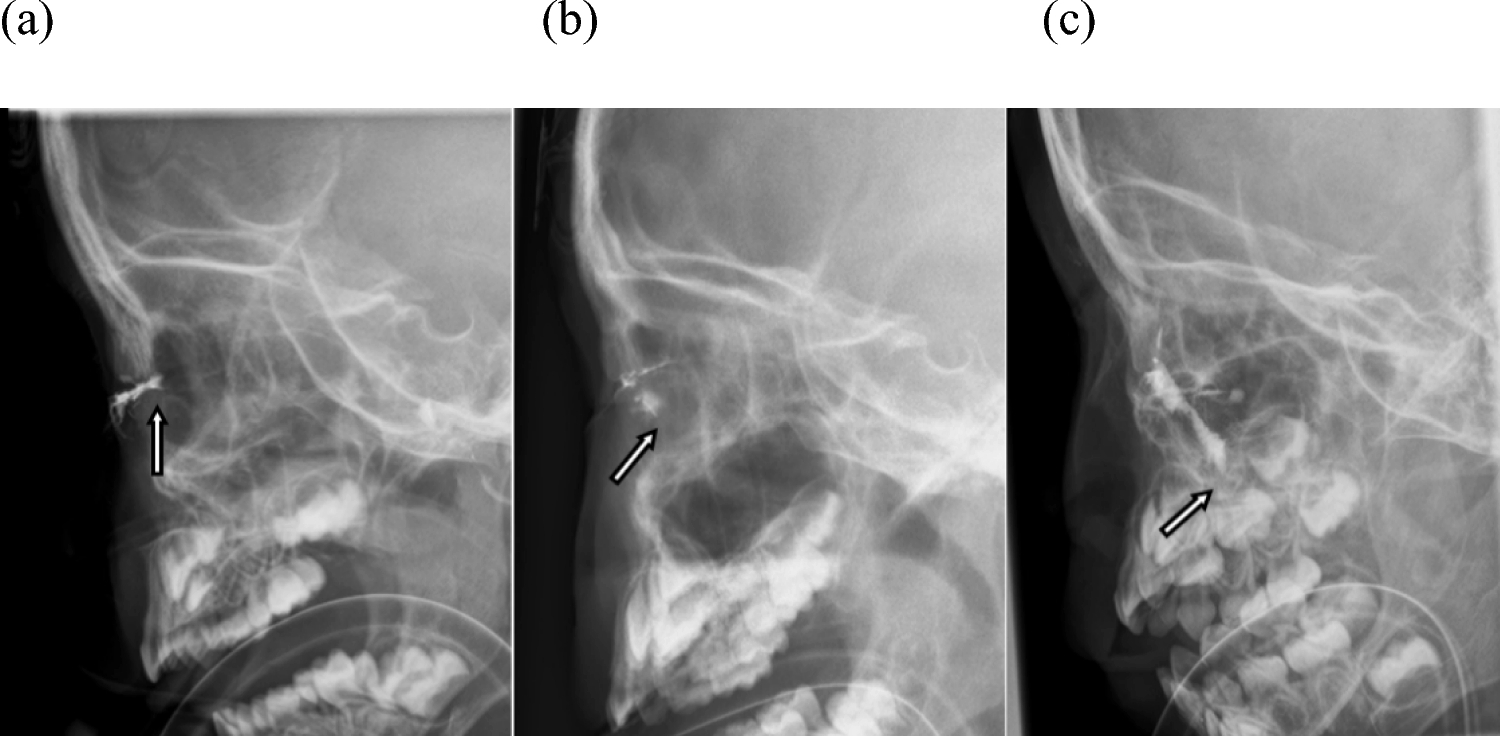

Clinical features and multimodal imaging of primary choroidal lymphoma

Fukutsu K, Namba K, Iwata D, Mizuuchi K, Kase S, Suzuki K, et al. Pseudo-inflammatory manifestations of choroidal lymphoma resembling Vogt–Koyanagi–Harada disease: case report based on multimodal imaging. BMC Ophthalmol. 2020;20:94.